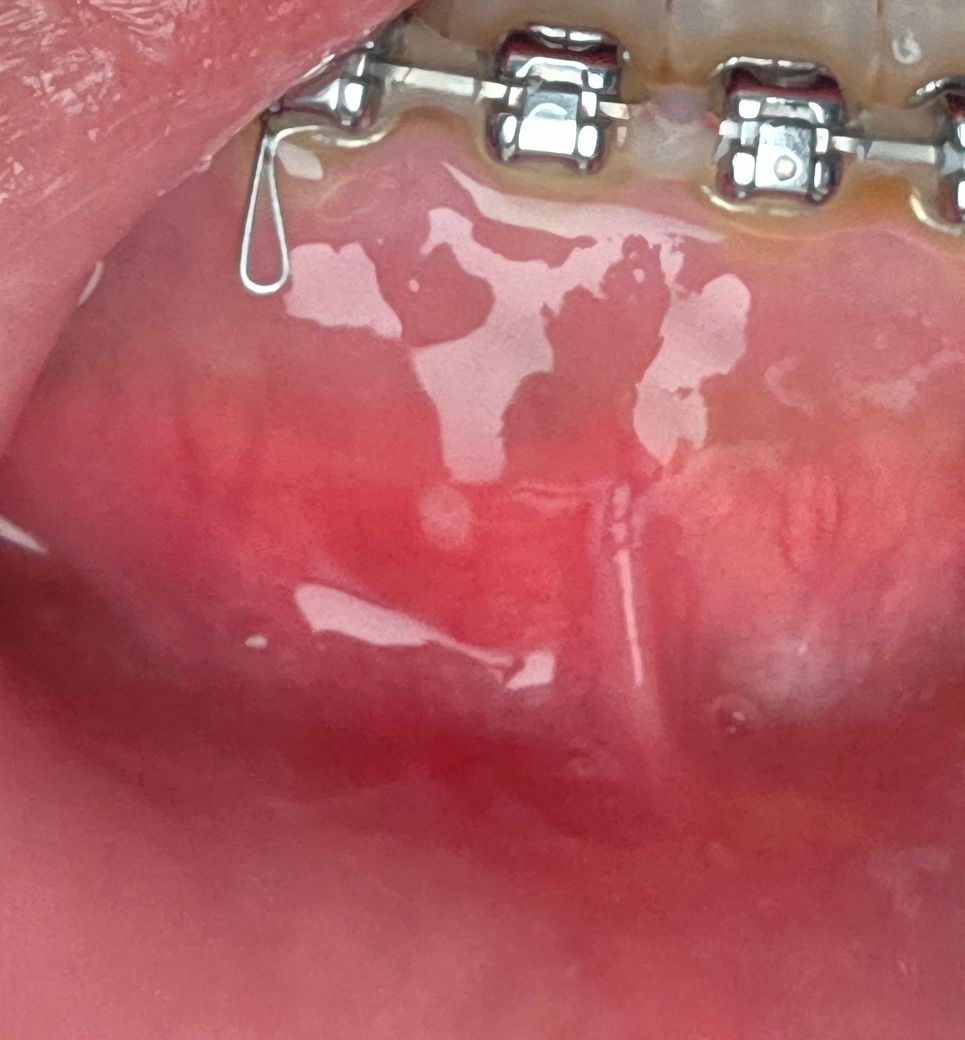

잇몸에 뭐가 났는데 이게 뭔가요???

잇몸이 저런게 나서 밥먹거나 할때 아파서 알보칠 칠했는데 나중에 검색 해보니 피스출라? 그런거 라고 하는거 같은데 치과를 가야 할까요??

누공(fistula)는 아니며 단순 아프타성 구내염(일종의 혓바늘)입니다. 그냥두면 저절로 없어집니다.

구내염으로 보여집니다. 자극적인 음식은 피하고 입안을 깨끗히 유지하고 수분섭취를 자주 합니다. 알보칠 사용하고 호전되지 않으면 치과에 내원하면 좋을것같습니다. 빠른 회복 바라겠습니다.

사진으로 보기엔 구내염의 가능성이 있어보입니다 오라메디나 디프람 연고 약국에서 사서 발라주세요